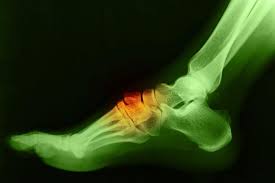

A bone spur (osteophyte) is an extra bony growth that develops along bones, often near joints or tendon attachments.

On top of the foot, this growth is called a tarsal boss or dorsal exostosis. While sometimes painless, it can cause discomfort when it rubs against shoes, tendons, or nerves.

Diagnostic imaging (X-rays, MRI, CT) confirms that the growth is a benign spur rather than a tumor.